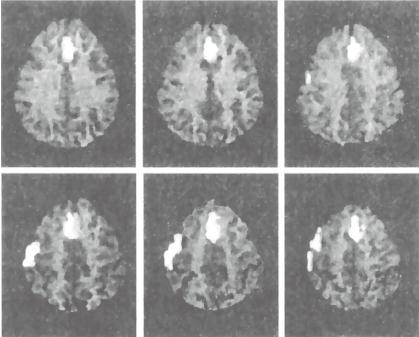

fMRI扫描的发现是清楚的。如你所见,在图6—2中,讲真话的被试只运用了一个脑区(前扣带回)。然而,在撒谎条件下,两个区域(前扣带回和背侧前额叶皮层)活动了起来。

图6—2 讲真话和撒谎被试的fMRI扫描结果

注:上图:讲真话(红心2)被试的脑扫描;下图:撒谎被试的脑扫描(梅花5)。

资料来源:见Langleben et al., 2002。